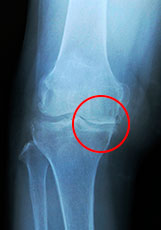

膝の病気には、若い人なら半月板損傷などの外傷や関節リウマチなども考えられますが、50代以降の方に多いのは、関節の変形を伴う変形性膝関節症です。これは膝の関節の軟骨がすり減ったために痛みがでてくる病気です。変形性膝関節症の可能性が疑われる場合は、まずレントゲンを撮って、「関節の変形があるか」、「変形は見られないが痛みを感じるか」などを確認します。

変形性膝関節症のX線

始めは動き始めるときに膝が痛みますが、そのうち動作中もずっと痛みが取れず、次第に歩くのが困難になります。特に階段を降りるときにつらいのが特徴です。関節が硬くなって膝の曲げ伸ばしが難しく、そのため「正座ができない」とか関節を覆っている滑膜が腫れて「膝に水がたまる」ということもあります。日本人の場合は、症状が進行すると骨が変形してO脚になる傾向が強く、生活に大きな支障をきたす場合もあります。 変形性膝関節症の原因としては、まずは肥満が考えられます。普段から、膝には体重の4~6倍の負荷がかかっていますので、肥満は膝にダメージを与える大きな原因の一つです。軟骨を長持ちさせるためには、適切な体重を維持することが重要です。とはいえ、変形性膝関節症の最も大きな原因は、加齢による変性です。長年使用してきた膝の関節は、歳をとると多かれ少なかれ不具合が生じてきます。なお、若い頃に外傷などで膝を痛めたり運動をやり過ぎたりした結果、軟骨に通常より多くの負担をかけた場合には、より症状が出やすいかもしれません。